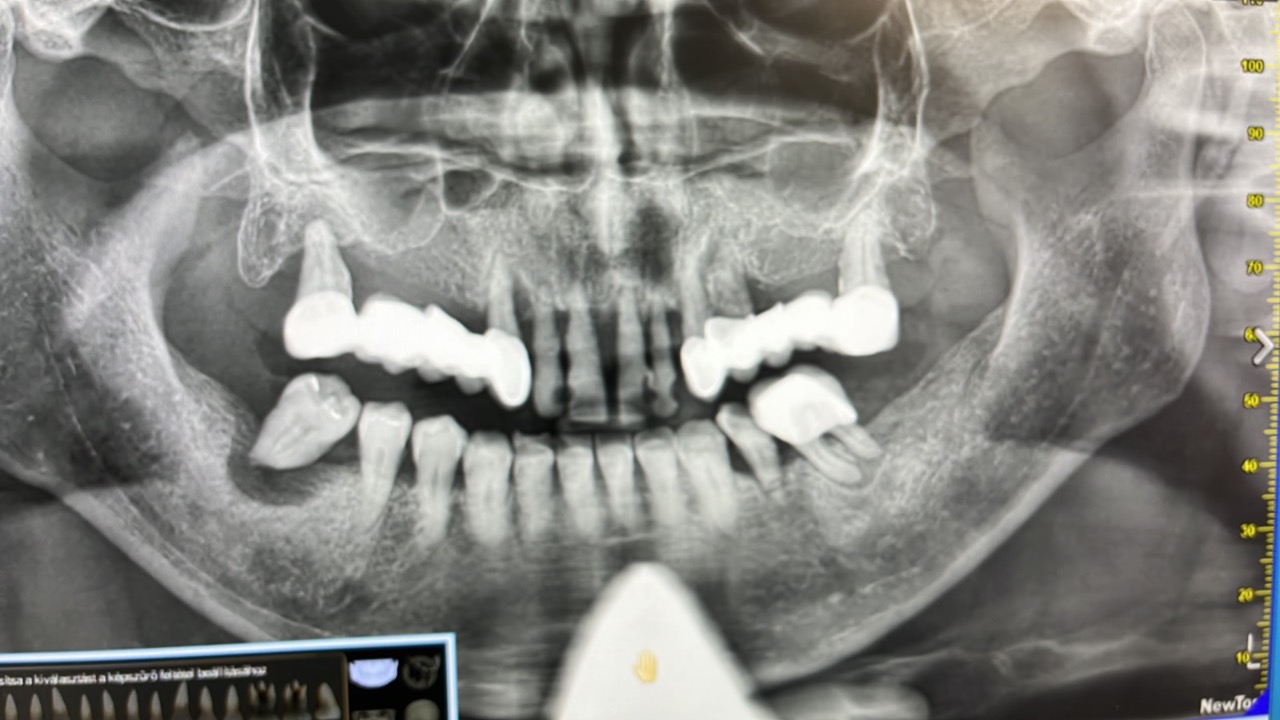

Az aktív fertőzés zavarhatja a csontintegrációt, a fogászati implantátum gyógyulását.…

A fogorvosi gyakorlatban többnyire akkor találkozunk a

góc gyanújával, amikor a belgyógyász vagy háziorvos ismeretlen hátterű CRP-emelkedés, hajhullás vagy bőrtünetek miatt utalja be a beteget góckutatásra.